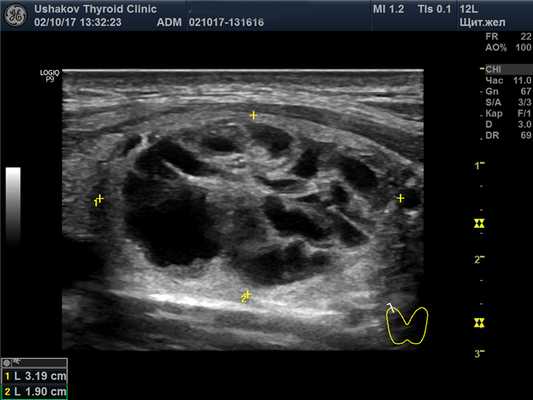

Структура паренхимы долей щитовидной железы неоднородная – узловая, вне узлов преобладает изоэхогенность.

В правой доле щитовидной железы в центрально-каудальной части почти до её краев (в поперечной проекции) расположен овоидоподобной формы узел 22,9х20,7х33,1 мм (7,4 мл), окруженный по всему периметру чёткой гипоэхогенной границей-контуром, значительно неоднородный за счет множественных анэхогенных (жидкостных) участков (около 70% от объёма узла), преимущественно с чёткими границами в виде узких перегородок с изо- и гиперэхогенной (фиброзной) тканью и изоэхогенной тканью по периметру узла; при ЭДК заметно примыкание к узлу с кранио- и каудальной сторон магистральных сосудов, и умеренный кровоток по части периметра и мало интенсивный внутри узла (в перегородках); при эластографии SR 2,8 (3,3 - в обл. некоторых перегородок). Вне узла ткань изоэхогенная, почти однородная; в краниальном полюсе 21,2х15х15,1 мм (2,3 мл), а также медиально. В режиме ЦДК и ЭДК кровообращение в этой ткани в малой степени усилено.

Рис. 27.5. Пример 1. (правая доля, поперечная проекция).

Латерально и вентрально за узлом – лишь тонкий слой ткани. Медиально заметна значимая часть внеузловой ткани. Узел в поперечной проекции подобен кругу. Чёткий гипоэхогенный контур по всему периметру узла.

Но ткань расположена ещё и вокруг узла (больше с медиальной стороны). Поэтому разница объёма доли и узла (11,4-7,4) показывает 4 мл, что составляет 35% от величины доли и также указывает на субтотальнодолевой узловой зоб.

4 мл макроструктурно полноценной ткани справа для этой пациентки являются абсолютной ценностью. На это указывает объём 3,2 мл левой доли. 7,2 мл всей макроструктурно полноценной ткани (без перешейка) соответствуют оптимальному объёму щитовидной железы у женщин. Поэтому важно в описании и заключении сообщать сведения о состоянии и величине этой ткани. В описании – конкретно, в заключении – общетерминологически.